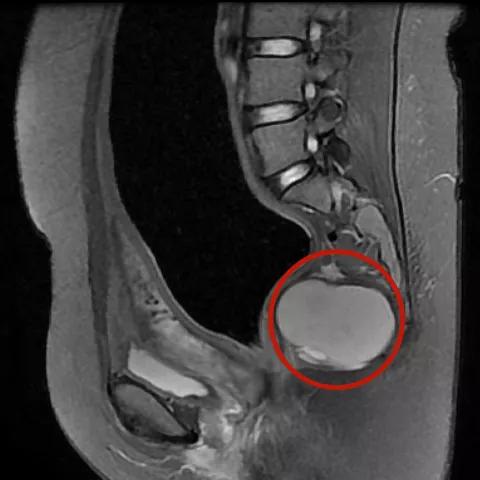

她的骶尾部还有个苹果大小的 囊性占位

△骶尾部囊性占位